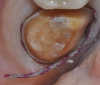

Figure 1: Example of an alginate impression.

Figure 1

As mentioned, alginates are hydrophilic, so the focus with them is not on keeping teeth dry, which is challenging with hydrophobic materials, but keeping them moist after the impression is taken to preserve accuracy.3 Many clinicians who are long familiar with this material find it accurate, easy to use, and patient-friendly. However, it requires accurate measurement and a thorough mixing of the materials; the additional need for careful attention to set-time accuracy is less challenging with the triphasic materials that are now available, as they change color to indicate when it is the correct time to seat the tray, and when to start timing the final set. Alginates should be poured quickly, and most can be poured only once (Figure 1). The clinician must also take care to avoid pulls, which can cause distortion during removal. Alginate impressions that are not poured immediately need to be stored in a moist environment. They can be wrapped in a wet paper towel or stored in a plastic box that is designed to contain humidity.